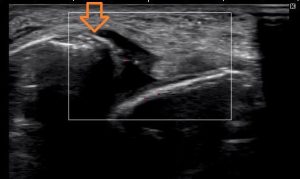

エコーで見るとこんな画像が・・・・・

矢印の先が折れている部分です。

白い線が骨です。まっすぐに線がつながってなければいけません。

しかし、矢印の先で離れてしまっているのわかりますか??

骨折と言っても、小さな骨が剥がれている感じです。